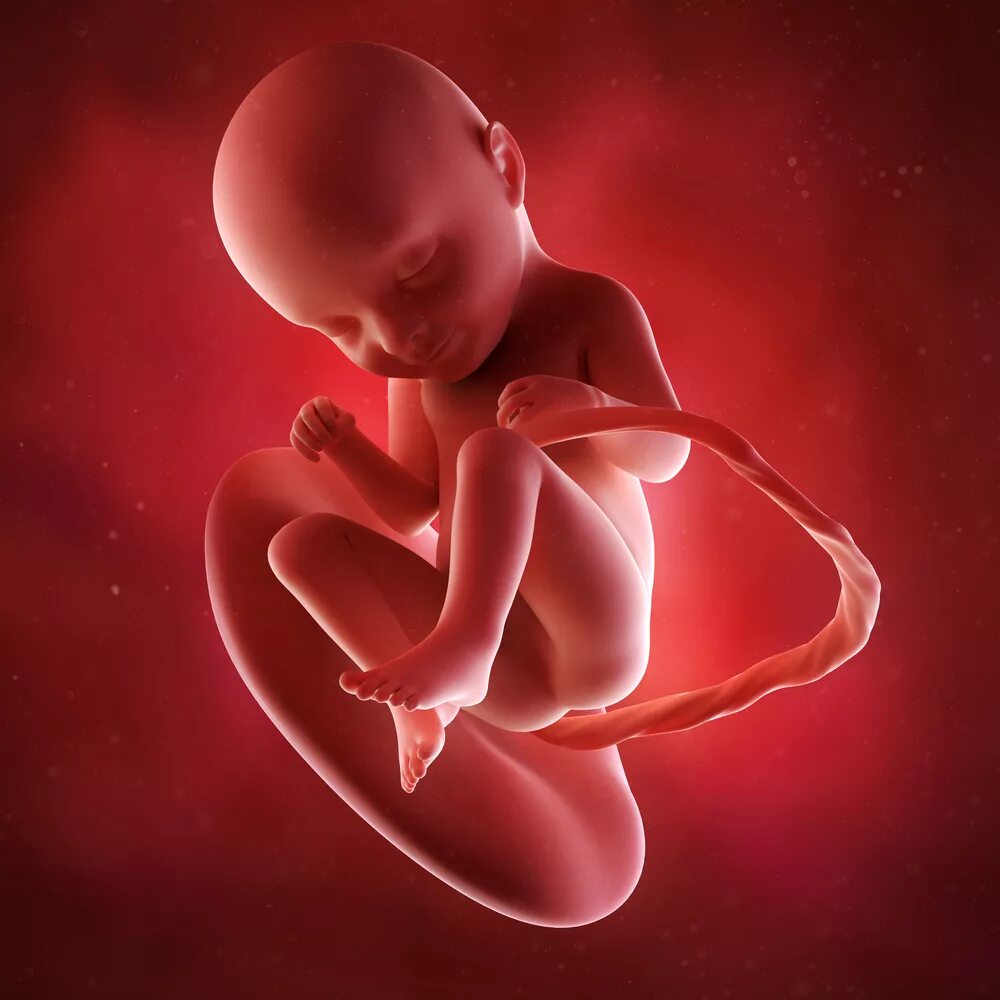

Плод 33